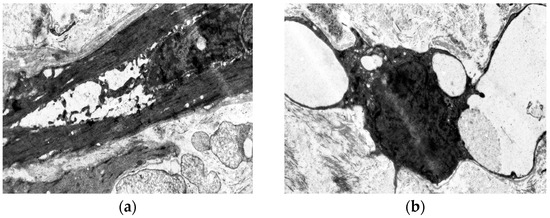

Age- and Varicose Disease-Associated Changes in the Muscular Components of the Great Saphenous Vein

by Khurshed A. Abduvosidov, Irina A. Chekmareva, Valeria G. Shestakova, Irina N. Shabanova, Alexander G. Alekseev, Edgar S. Kafarov, Alexander A. Palalov, Irina N. Yashina and Evgeny N. Galeysya

J. Clin. Med. 2025, 14(18), 6448; https://doi.org/10.3390/jcm14186448 - 12 Sep 2025

Varicose disease and other age-related vascular illnesses are extremely prevalent among the adult population. Despite this, research devoted to involutive changes in the veins of the lower extremities is rare and fragmented. Complex morphological evaluation of the wall of the vein related to [...] Read more.

Varicose disease and other age-related vascular illnesses are extremely prevalent among the adult population. Despite this, research devoted to involutive changes in the veins of the lower extremities is rare and fragmented. Complex morphological evaluation of the wall of the vein related to age and varicose disease can add valuable data to fundamental geriatric and vascular medicine. Objectives: The study was designed to determine the age-related changes in the muscular component of the great saphenous vein and changes associated with varicose disease. Materials and Methods: A morphological study of a specimen of the great saphenous vein was conducted on 55 deceased individuals and 80 patients with varicose disease. Four age subgroups were identified: young, middle-aged, elderly, and senile. A total of 135 fragments of the great saphenous vein were evaluated. Histological, morphometric, and electron microscopic studies were performed. A quantitative analysis of the volumetric fraction of muscular components was calculated using the Shapiro–Wilk test, Kruskal–Wallis (ANOVA) and Mann–Whitney methods with Bonferroni correction. Results: Our study showed that the amount of connective tissue elements between bundles of smooth muscle cells increased with age. In patients with varicose disease, we observed an appearance of connective tissue fibers among smooth muscle cells, more pronounced with the disease progression. The structure of smooth muscle cell changes. Thus, we observed hypertrophy and phenotypic heterogeneity of cells with subsequent destruction of communicative contacts. The values of subintimal longitudinally arranged smooth muscle cells reached their maximum in middle age in both normal and varicose veins, while significant decrease occurred in elderly and senile patients. Quantitative indicators of circularly arranged smooth muscle cells of the middle layer did not change with age but significantly decreased in varicose disease. Age-related changes are characterized by an increase in the proportion of smooth muscle cells in the outer layer. In varicose veins, in young and middle-aged patients, the content of bundles of longitudinally arranged smooth muscle cells in the outer layer was higher compared to the age norm, with a significant decrease in senile age. Conclusions: The age norm of the muscular component of the great saphenous vein wall is characterized by an increase in the volumetric fraction of subintimal longitudinally arranged smooth muscle cells in middle age, the volumetric fraction of circularly arranged smooth muscle cells of the middle layer remains unchanged, and the volumetric fraction of bundles of longitudinally arranged myocytes of the outer layer increases. With age in varicose disease, sclerotic changes progress in the structure of the great saphenous vein at the tissue, cellular, and intracellular levels, leading to a decrease in the volumetric fraction of all muscular components of the great saphenous vein structure. Full article